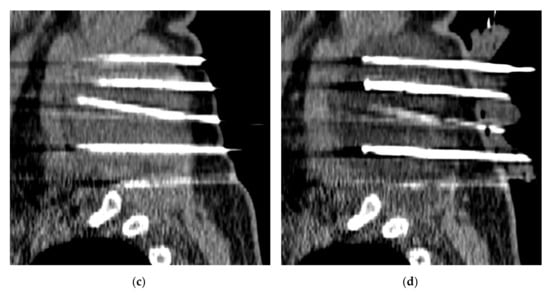

DFS was 90% at 3 months and 62% at 6 and 12 months for all patients (Figure 3).

Figure 3.

Kaplan–Meier disease-free survival (DFS) curve for EAD tumors after curative and partial CA treatments, up to 12-month MRI follow-up.